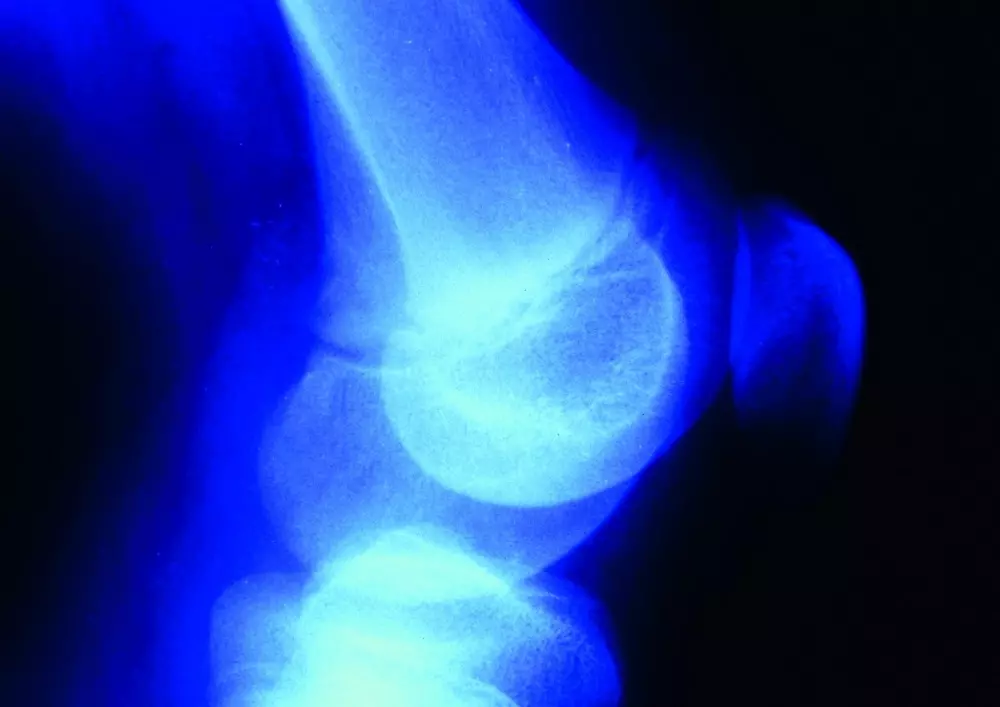

Boczne przyparcie rzepki

Polecamy także tekst pt. „Postępowanie rehabilitacyjne w bocznym przyparciu rzepki. Cz. 1: Przyczyny anatomiczne”. Dr Wojciech Dubaj wskazuje, że boczne przyparcie rzepki w pierwszej fazie często bywa nierozpoznane przez brak widocznych zmian struktury rzepki oraz okolicznych struktur miękkich w badaniach obrazowych, a kolejnym etapem jest już chonodromalacja rzepki. Ponadto wskazuje, że zazwyczaj są to te same jednostki chorobowe oceniane z różnych perspektyw. Opracowanie zawiera opis przyczyn anatomicznych tej dysfunkcji oraz przyczyny rozwoju zespołu bocznego przyparcia rzepki od stopy wraz z odpowiednimi ćwiczeniami.